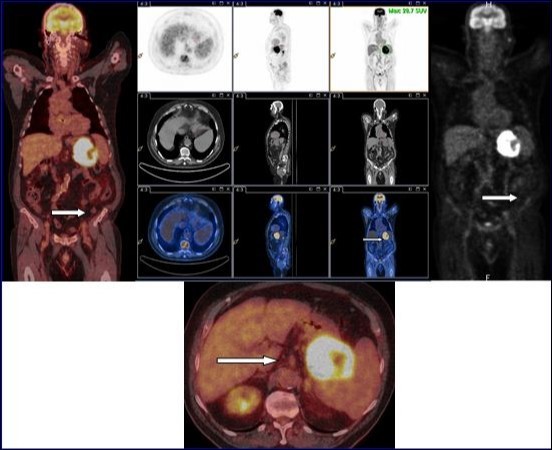

18F-FDG PET-CT with injection of intravenous iodinated contrast demonstrated an intense and diffuse hyper metabolism at the primary tumor of the stomach. No morphological or metabolic argument features of secondary manifestation of this tumor were observed in the whole-body (Figure 2). Partial gastrectomy with resection of the proximal 2/3 of the stomach, the spleen, the body and tail of pancreas and the left transverse colon was performed.

Figure 2.18F-FDG PET-CT with injection of intravenous iodinated contrast demonstrated an intense and diffuse hyper metabolism at the primary tumor of the stomach. No morphological or metabolic argument features of secondary manifestation of this tumor were observed in the whole-body.